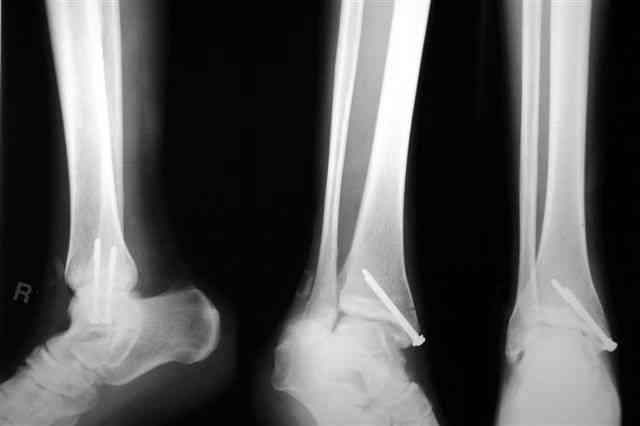

Лодыжку так ипрооперировал двумя 3.5 мм шурупами пришлось открыть - закрыто не удалось адекватно отрепонировать, при открытии - надкостничная

интерпозиция.

Бедро фиксировал длинной DCS.

По типу бриджинг плэйтин, крюком удалось низвести малый вертел и фиксировать винтом для восстановления медиальной стенки.

В приложении отправляю послеопер. снимки бедра и лодыжки обсуждаемого вчера больного.